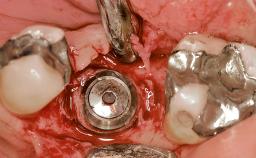

Early Placement of an Implant in a Maxillary Right Central Incisor Site

Type of Implants Two-Piece

Attachment Two-Piece

Bone Augmentation Horizontal|Simultaneous

Augmentation Materials Autogenous chips|Xenogenous|Membrane

Abutment Type Customized

Prosthesis Type FDP